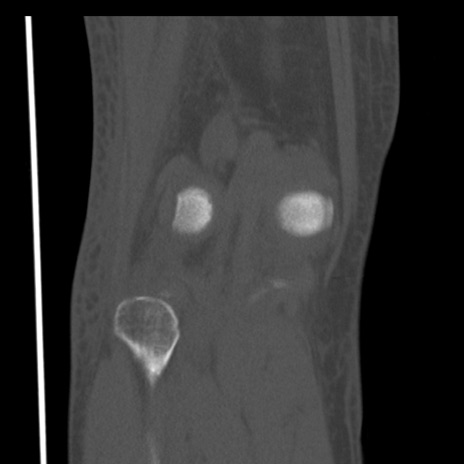

右膝関節CT

矢状断像